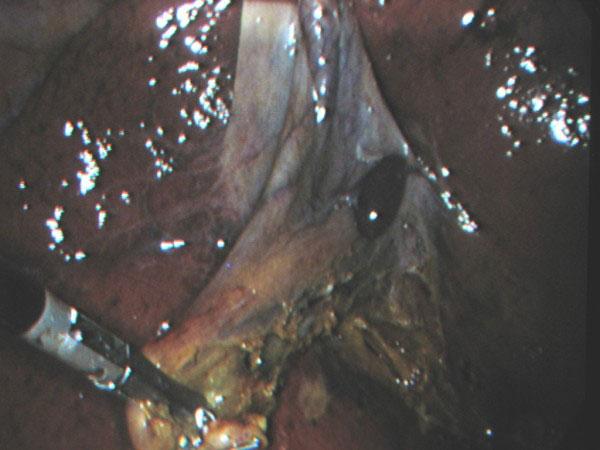

We describe the case of a 54-year-old woman who was found to have a nodule attached to the gallbladder wall without any connection with the main liver, during an elective laparoscopic cholecystectomy for gallstone disease. The nodule was removed with the gallbladder and identified histologically as normal ectopic liver tissue.

我们描述了一名54岁女性的病例,该患者在因胆结石疾病接受择期腹腔镜胆囊切除术时,发现胆囊壁上附着一个与主肝无任何连接的结节。该结节与胆囊一并切除,经组织学鉴定为正常异位肝组织。